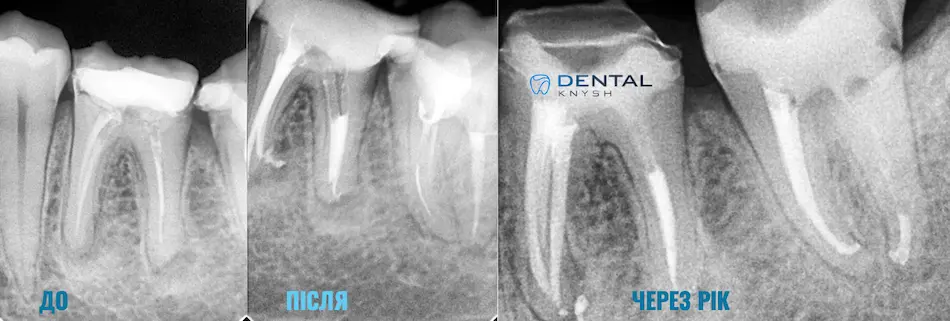

Фото-звіт ендодонтичного лікування: до/після, і через рік 2026-04-16